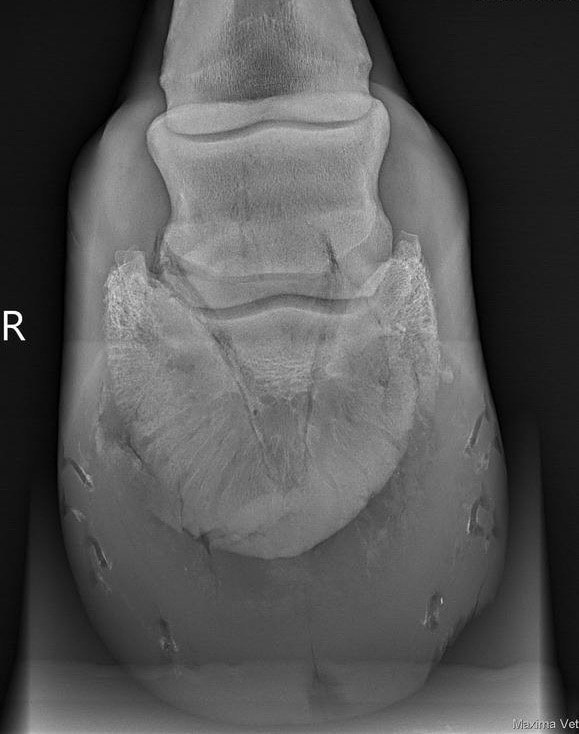

На рентгеновских снимках не было выявлено изменений.

МРТ-исследование позволило поставить сразу несколько диагнозов:

- Десмит коллатеральной связки;

- Остеосклероз дистального эпифиза третьей пястной кости;

- Дефект хряща дистального эпифиза третьей пястной кости;

- Десмит ножки межкостного мускула

Более точная диагностика позволяет проводить лучшее лечение и помогает

определить период реабилитации. Интересно, что эти изменения достаточно

явные для МРТ - не будут так заметны на других методах визуализации.